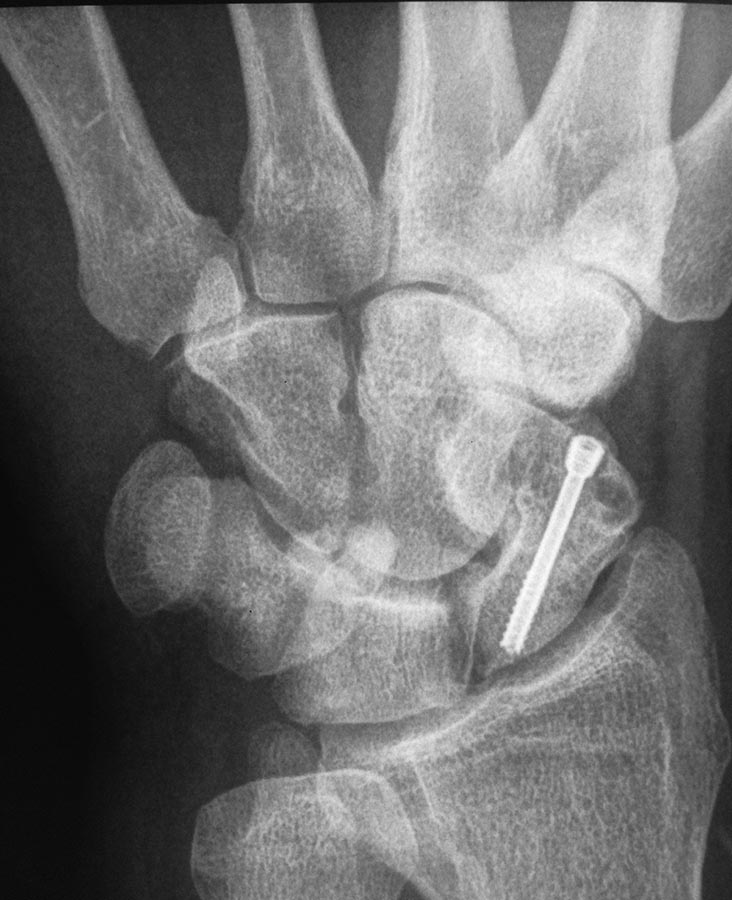

Здравствуйте. Мужчина 30 лет. Травма около 5ти лет назад

МОС винтом, в данное время в проекции ладьевидной кости болей нет, осевая нагрузка на 1ю пястную кость безболезненная, боли беспокоят при пальпации в проекции трехгранной кости и движениях в лучезапястном суставе(при пассивных и активных движениях возникают острые боли, так же в проекции трехгранной кости). На МРТ отмечаются проблемы в этой зоне. Со слов пациента, при периодических болях принимает таблетку найза, после чего все проходит.

Похоже на остеоид-остеому. Аспириновую пробу провести бы, хотя найз тоже вроде бы сыграл свою роль.

На 3/4 проекции с гороховидно-трехгранным суставом все в порядке. Хондроматоза не видно, а видно, что очаг "затемнения" на трехгранной кости сместился медиально, то есть он расположен на тыльной поверхности трехгранной кости, там, где и болит больше всего. И,во-вторых, даже если бы это был хондроматоз указанного сустава, то: с какой целью необходимо удалять гороховидную кость?